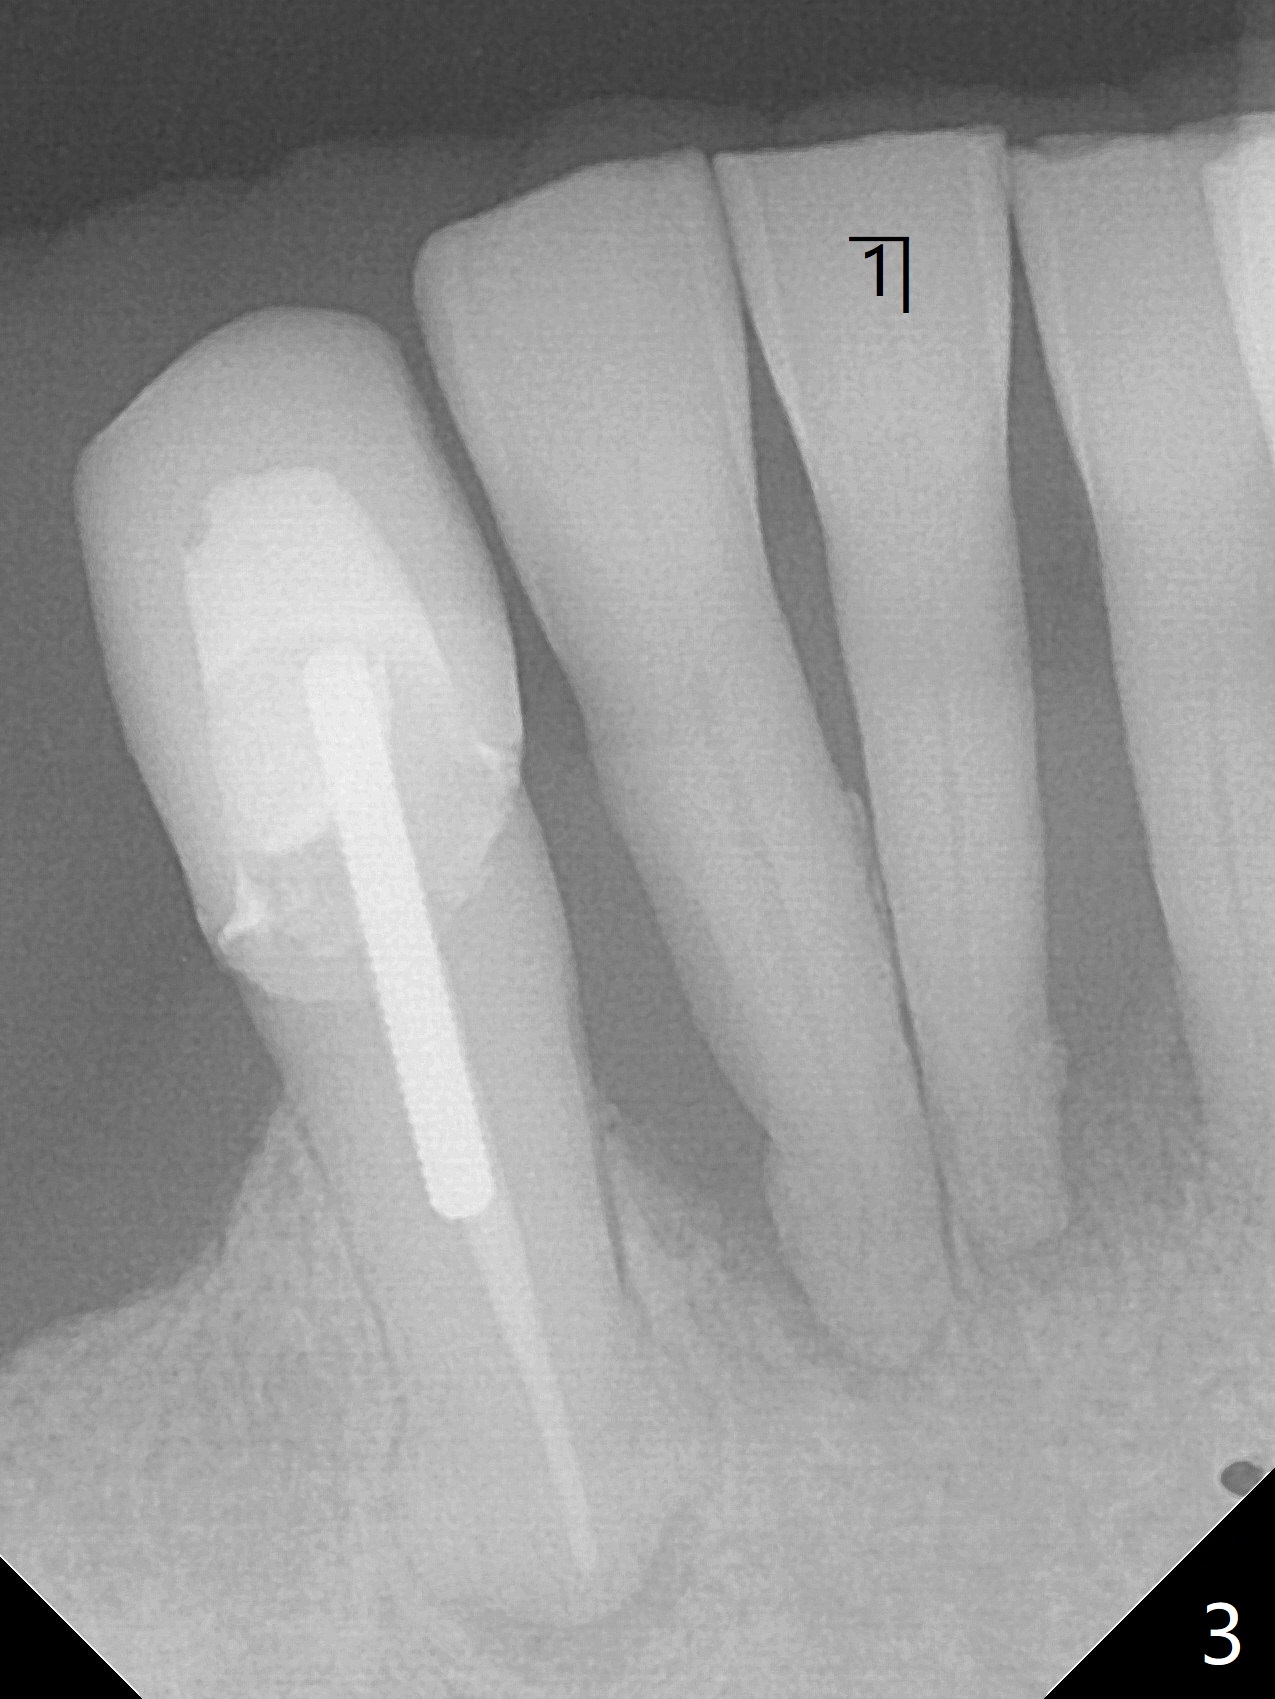

70岁男有上颌全口义齿,下颌局部义齿,后者由于右下切牙肿痛,松动无法戴入(图一至三),左下1骨质吸收严重,但是没有症状(图四)。理想治疗拔除右下1,2,即刻植牙,预防右下三断裂,不过病人没有思想准备,同意即刻植骨(图五,6个月吸收膜)。右下1舌侧,2颊侧脓肿(图一,二),拔牙时发现相应骨质缺损严重。四个月后在右下2植牙,做悬臂桥。当左下1不行时,做单个植牙,这样病人至少可以暂时使用局部托牙。